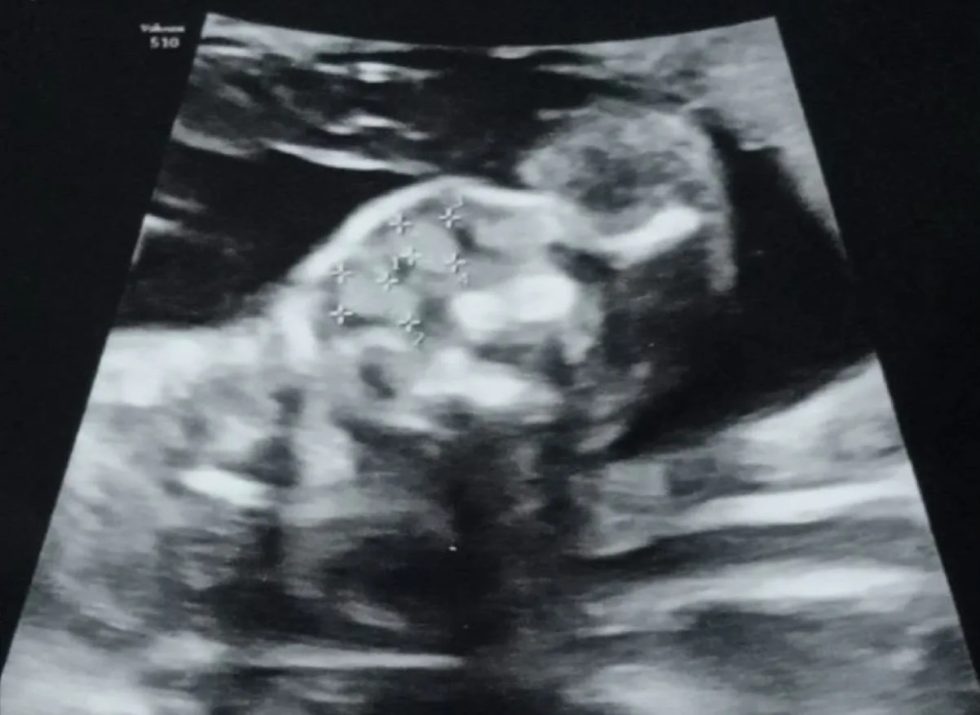

В основе программного продукта — инновационная шкала, анализирующая ключевые параметры щитовидной железы плода, полученные в ходе УЗИ: структурные особенности, размеры, периметр и объем. Система автоматически подсчитывает сумму баллов и выводит результат в диалоговое окно.

Программа (патент № 2025 664 176) открывает широкие возможности как для научного сообщества, так и для практикующих врачей. Ее применение позволяет с высокой долей вероятности определить наличие или отсутствие рисков развития аномалий органа. Полученные данные станут важным подспорьем для медиков при планировании тактики ведения родов, дополнительном обследовании новорожденного и его динамическом наблюдении, особенно в случаях выявленных отклонений.

Фото: ОрГМУ